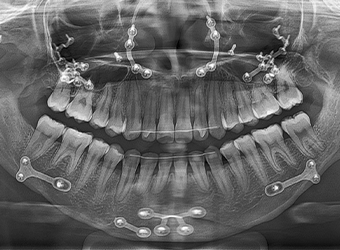

얼굴 턱뼈 수술에서는 절단 후 분리된 뼈를

새로운 위치에 고정하기 위해 고정핀을 사용합니다.

이 핀은 뼈가 충분히 회복된 후, 핀제거 수술을 통해 제거할 수 있습니다.

• X-ray, CT 등

방사선 촬영에서 핀이

보이고 싶지 않은 경우